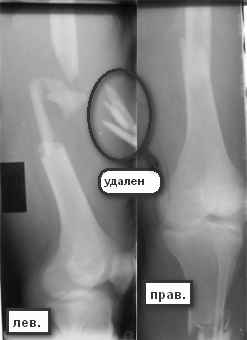

Больной 29 л 23 февраля на мопеде въехал в легковой автомобиль (естественно, больной

пьяный). Поступил с диагнозом: закрытый перелом правого бедра в с/з-н/з, открытый перелом

правой голени в в/з (рана в проекции перелома до 3 см), открытый оскольчатый перелом левого

бедра в с/з с дефектом костной ткани (рана до 12 см по наружной поверхности бедра). ПО

дежурству - ПХО ран, стержневые аппараты на оба бедра, аппарат Илизарова на правую голень. По

стабилизации состояния - домонтаж аппарата Илизарова с окончательной репозицией. Спустя 2

недели - открытая репозиция отломков правого бедра, интрамедуллярный остеосинтез

стержнем с дистальным блокированием. С правой ногой разобрались. Вопрос встает о том что

делать с левой. При ревизии раны левого бедра (при поступлении) удален торчащий из раны

свободный осколок до 6х3 см,загрязненный травой,пылью.Со слов скорой - на месте

происшествия вроде как были еще мелкие костные осколки. Осколки что на снимке лежат по

внутренней поверхности бедра, связаны с м/тканями, дефект кости до 7-8 см по длине. Массы

осколков явно не хватает для его заполнения. Кроме того массивное скелетирование основных

отломков (до 7-10 см в обе стороны). Все раны зажили без проблем. Наши планы - открытая

репозиция левого бедра, ИМО с укорочением. Потом когда (если)срастется пусть занимаются